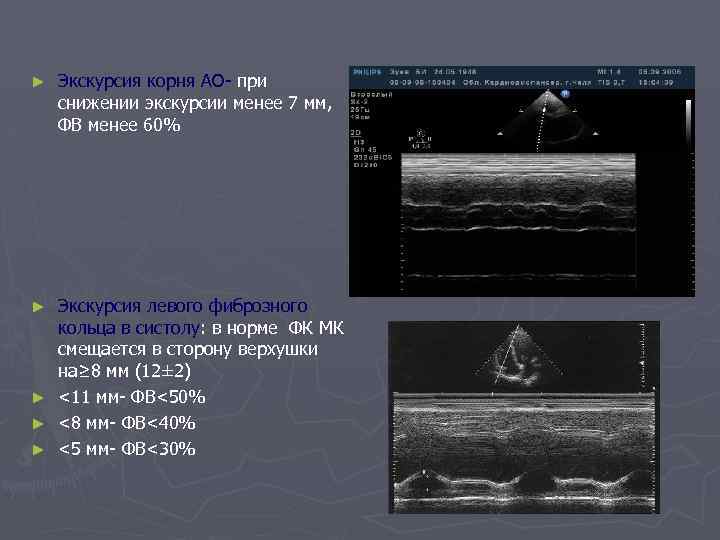

► Экскурсия корня АО- при снижении экскурсии менее 7 мм, ФВ менее 60% Экскурсия левого фиброзного кольца в систолу: в норме ФК МК смещается в сторону верхушки на≥ 8 мм (12± 2) ► <11 мм- ФВ<50% ► <8 мм- ФВ<40% ► <5 мм- ФВ<30% ►